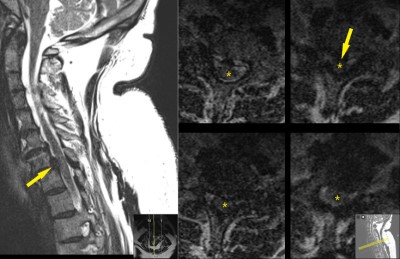

C-spine MRI. Midsagittal image (left) shows C7-T1 malalignment and disc displacement (yellow arrow). Axial images (left) are degraded by patient motion during the MRI scan. They show probable disc displacement and cord compression at C7-T1, but are inadequate to plan surgery. Disc displacement is shown by yellow arrow and spinal cord is designated by yellow star.